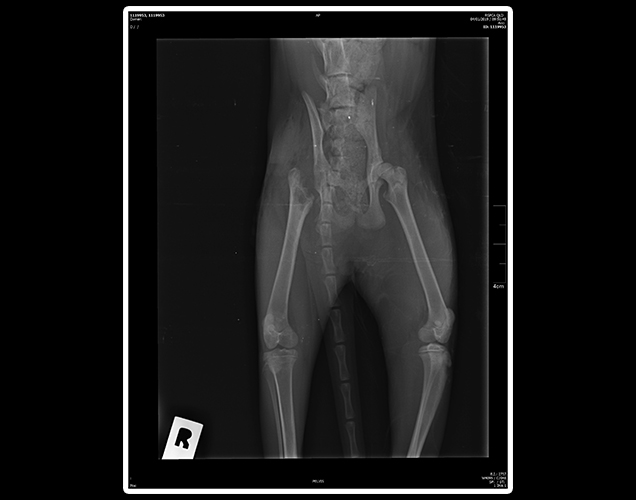

The veterinarian examination showed that Maple had breathing distress, a low temperature, fluid around the lungs and bruising of the lung with three fractured ribs on the right and one on the left.